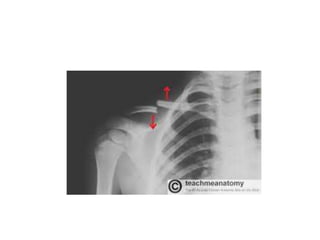

• Fractures of clavicle are very common at the

junction between middle &lateral 1/3 often from

indirect force.The medial fragment becomes

elevated by sternocleidomastoid. The lateral

fragment sags down from the weight of the arm ,

but also adducted especially by P.Major.

• Acromial-clavicular disruptions are also common

with torn acromial clavicular &coracoclavicular

ligaments >diastasis of the joint.